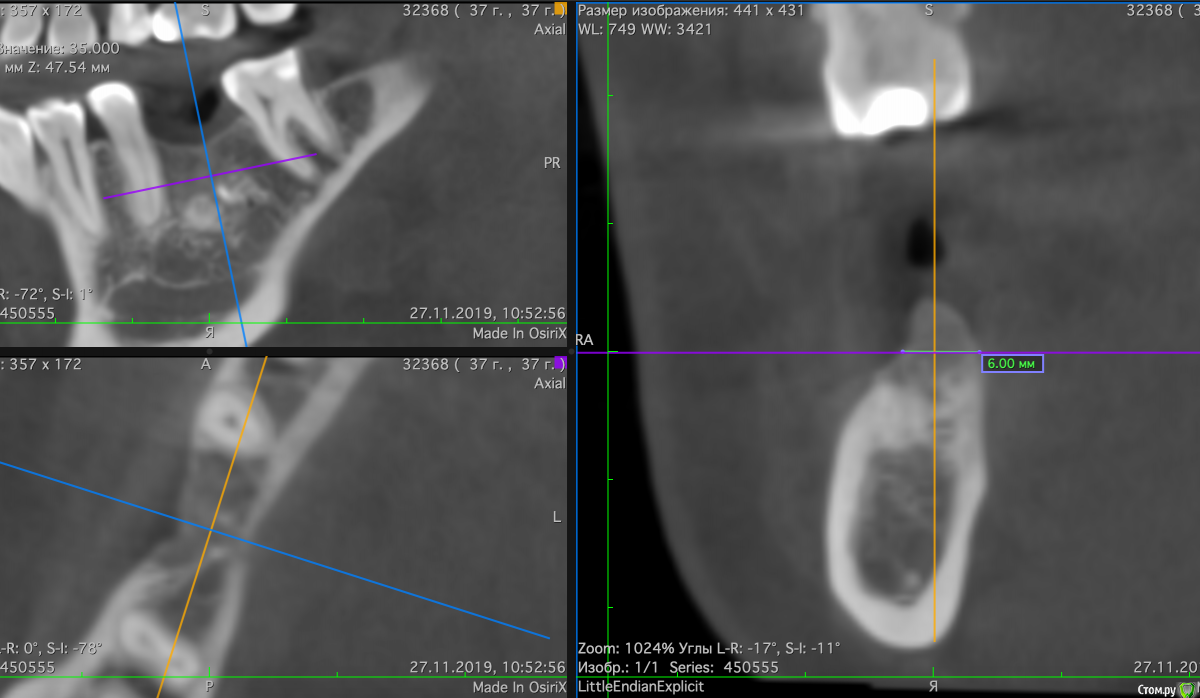

Valerkaa Опубликовано 14 декабря, 2019 Поделиться Опубликовано 14 декабря, 2019 (изменено) Уважаемые доктора, помогите, пожалуйста, советом. Опыт в имплантации небольшой, хотелось бы принять правильное решение.Планируется имплантация в области отсутсвующего 4.6. Помимо остатков выведенного материала (думаю, уйдет при формировании ложа), есть недостаток по ширине. Подумываю над имплантацией+одномоментно кость+мембрана. Или лучше разбить в 2 этапа и сделать "сосиску"? Также подумывала над резекцией гребня по высоте, но думаю, слишком уж большой вертикальный дефект получится (около 4мм). Изменено 14 декабря, 2019 пользователем Valerkaa Ссылка на комментарий

Valerkaa Опубликовано 15 декабря, 2019 Автор Поделиться Опубликовано 15 декабря, 2019 Большое спасибо. Вот с размерами. №1 и №2 Ссылка на комментарий

Valerkaa Опубликовано 7 января, 2020 Автор Поделиться Опубликовано 7 января, 2020 я не делаю редукцию, ставлю глубоко + бонпрофайлером (в некоторых системах бонмил) создаю профиль прорезывания в кости, для абатмента. В данной ситуации ставил бы BL имплантат.если нетрудно, подскажите пожалуйста. Если ставить глубоко + бонпрофайлер, то насколько глубоко?если на глубине, где ширина альвеолярной части около 6мм, то относительно соседних зубов кажется очень глубоко это... Ортопед не будет материться?) Ссылка на комментарий